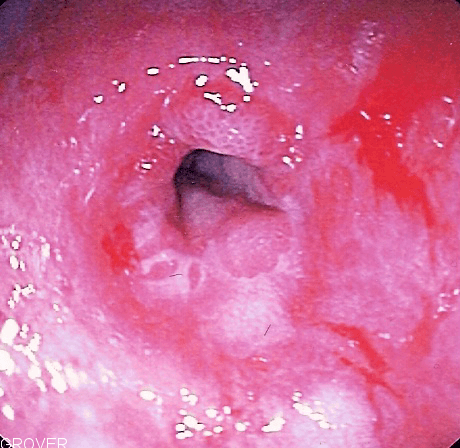

A benign esophageal stricture, or peptic stricture, is a narrowing or tightening of the esophagus that causes swallowing difficulties. Symptoms of esophageal strictures include heartburn, bitter or acid taste in the mouth, choking, coughing, shortness of breath, frequent burping or hiccups, pain or trouble swallowing, throwing up blood, or weight loss. It can be caused by or associated with gastroesophageal reflux disease, esophagitis, a dysfunctional lower esophageal sphincter, disordered motility, lye ingestion, or a hiatal hernia. Strictures can form after esophageal surgery and other treatments such as laser therapy or photodynamic therapy. While the area heals, a scar forms, causing the tissue to pull and tighten, leading to difficulty in swallowing. It can be diagnosed with an X-ray while the patient swallows barium (called a barium study of the esophagus), by a computerized tomography scan, a biopsy, or by an endoscopy. If it is caused by esophagitis, in turn caused by an underlying infection, it is commonly treated by treating the infection (typically with antibiotics). In order to open the stricture, a surgeon can insert a bougie – a weighted tube used to dilate the constricted areas in the esophagus. It can sometimes be treated with other medications. For example, an H2 antagonist (e.g. ranitidine) or a proton-pump inhibitor (e.g. omeprazole) can treat underlying acid reflux disease. Gastroesophageal reflux disease (GERD) affects approximately 40% of adults. Strictures occur in 7–23% of patients with GERD who are untreated.